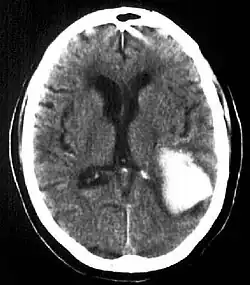

| Multiple intraparenchymal hemorrhage | |

Intraparenchymal hemorrhage is one form of intracerebral bleeding in which there is bleeding within brain parenchyma. The other form is intraventricular hemorrhage).[1]

Intraparenchymal hemorrhage accounts for approximately 8-13% of all strokes and results from a wide spectrum of disorders. It is more likely to result in death or major disability than ischemic stroke or subarachnoid hemorrhage, and therefore constitutes an immediate medical emergency. Intracerebral hemorrhages and accompanying edema may disrupt or compress adjacent brain tissue, leading to neurological dysfunction. Substantial displacement of brain parenchyma may cause elevation of intracranial pressure (ICP) and potentially fatal herniation syndromes.